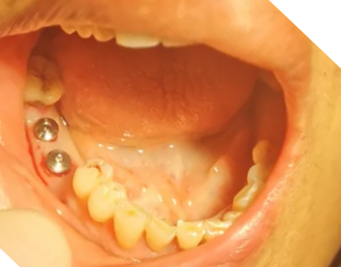

張教授采用美國目前流行的微創(chuàng)種植手術(shù),在短短的10來分鐘內(nèi),完成2顆JTK金泰克種植牙的植入手術(shù),贏得了醫(yī)護人員及患者的當眾稱贊!患者當場表示驚訝,并要求醫(yī)生再撥掉另外兩顆已經(jīng)搖動的恒牙,下期再種!

金泰克種植體的微創(chuàng)手術(shù),不僅能極大縮短手術(shù)時間,減少病人的痛苦和手術(shù)感染的風(fēng)險,也減少牙醫(yī)在手術(shù)臺上的體力耗損,而且微小的創(chuàng)口也讓無痛植牙技術(shù)成為現(xiàn)實,病人手術(shù)體驗極佳。金泰克種植體系統(tǒng)的免二期手術(shù),簡便的牙冠修復(fù)技術(shù),能確保牙醫(yī)能在很短的時間內(nèi)掌握牙種植技術(shù),安全可靠地為缺牙患者裝上第三副牙(種植牙)。